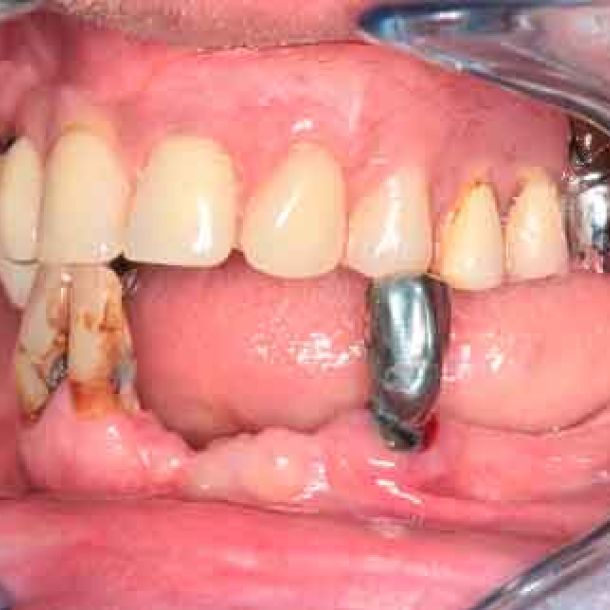

Patient de 66 ans. Souhaite retrouver un confort fonctionnel et améliorer l'esthétique.

Les structures parodontales des dents restantes ne sont plus suffisantes. Une édentation est envisagée. Le plan de traitement est orienté vers une prothèse complète maxillaire amovible et une prothèse complète mandibulaire supportée par des implants. Le défi est de passer de la situation initiale aux provisoires en utilisant les données du patient.

Photo - Situation intra-orale

Modèles 3D - Occlusion obtenue par la caméra intra-orale